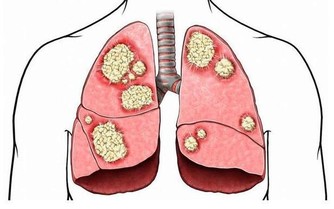

3.預防疾病

這種從肛門排出的廢氣,有時會帶有臭味;這是因為排氣時人體會釋放少量氫化硫,而這種物質具有防止細胞受損的作用,甚至可以預防心血管疾病和中風。

6.疾病的預警信號

在放屁時不應出現不適感,氣味雖然難聞但不會極端惡臭。如果發現自己在排氣時,明顯感到腹痛,或是氣味比較異常,那麼應當立即去醫院進行相應檢查,食物不耐受和結腸癌等疾病都會引起這類病症。